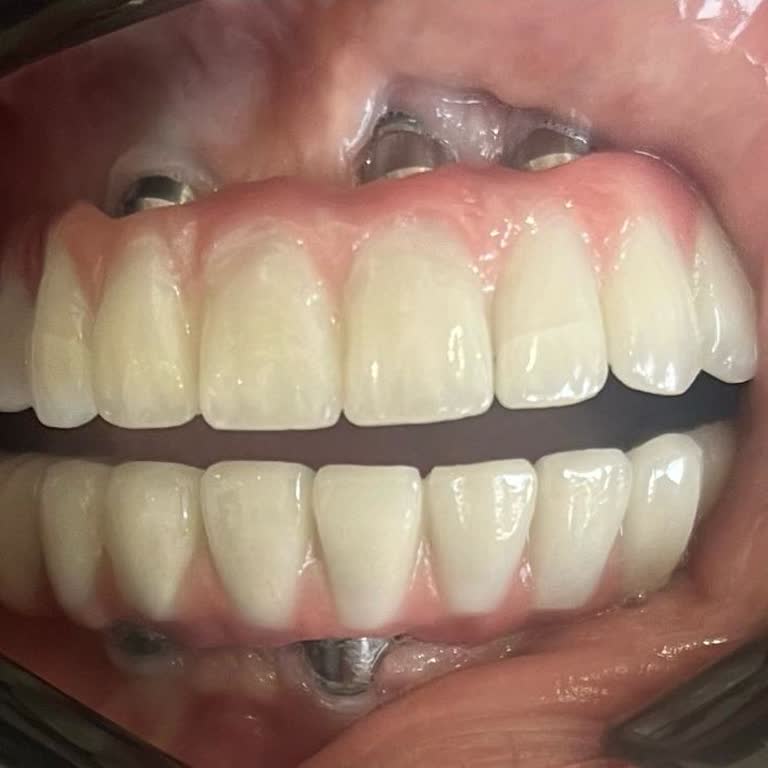

Yaklaşık 5 yıl önce Yeşiltepe Kliniği’nde Osstem implant yaptırdım ve bu süre boyunca implantımı sorunsuz olarak kullandım. Ancak 25.02.2025 tarihinde kemiğe saplı olan kısımda çatlama oldu, implant tamamen düştü ve ciddi mağduriyet yaşadım. Yaşanan bu ciddi arızaya rağmen klinik ve ilgili kişiler ...